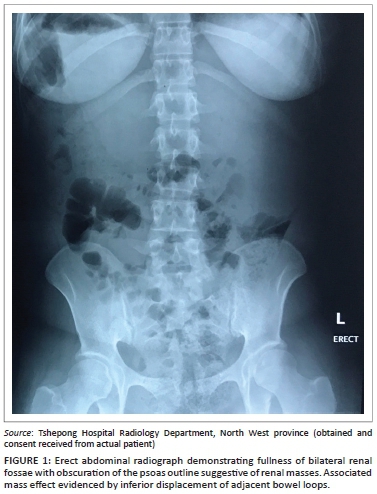

An erect abdominal radiograph demonstrated fullness in bilateral renal fossae with obscuration of the psoas outlines, as shown in Figure 1. A bedside ultrasound performed by the attending clinicians revealed bilateral encapsulated renal cysts. A working diagnosis of polycystic kidney disease was made. A subsequent ultrasound was then repeated in the radiology department, showing bilateral subcapsular renal collections with low-level internal echoes (Figure 2). A contrast CT study of the abdomen was performed and demonstrated large bilateral subcapsular perirenal collections with the fluid measuring 24 Hounsfield units (Figure 3a and 3b). Additional findings included compression and anatomical distortion of the kidneys.